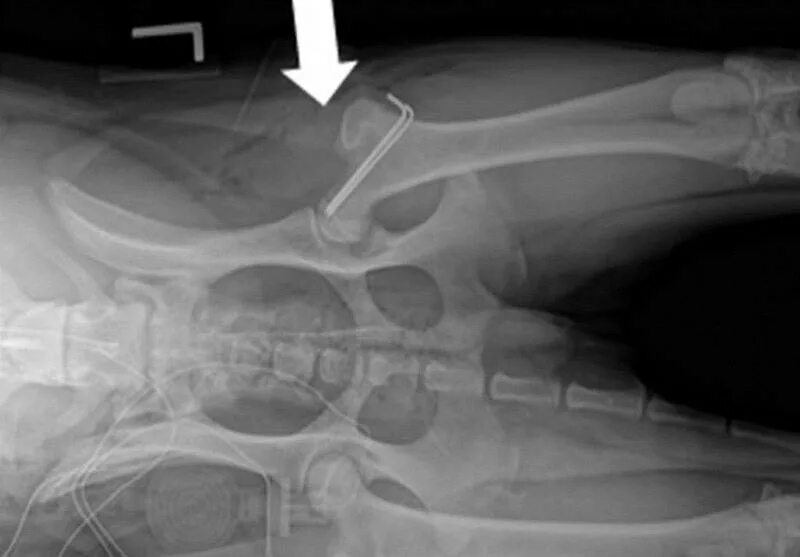

Операция суставов собак